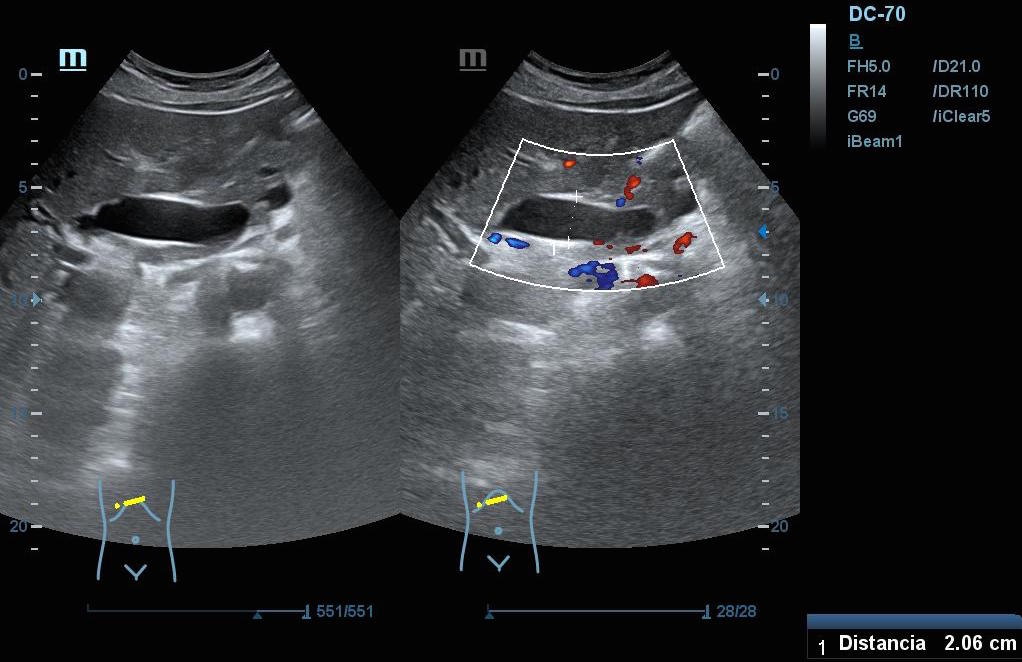

Hallazgos ecográficos: En el epigastrio se observa una imagen anecoica tubular, sin captación en Doppler, con un diámetro mayor a 2 cm, que sugiere una dilatación del colédoco (imagen 1). La vesícula biliar se encuentra completamente distendida y hepatizada, con una imagen en «doble cañón de escopeta» sugestiva de colestasis (imagen 2). En los cortes longitudinales se identifica una masa anterior a la aorta en el corte paramedial izquierdo, aparentemente localizada en el cuerpo del páncreas (imagen 3). En los cortes transversales se observa una masa que afecta tanto al cuerpo como a la cabeza del páncreas (imagen 4).